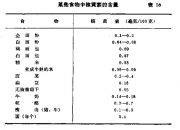

| 2021年7月26日 (一) 20:03 | 维生素需要量.jpg (文件) |  |

131 KB | Uploaded with SimpleBatchUpload | 3 |